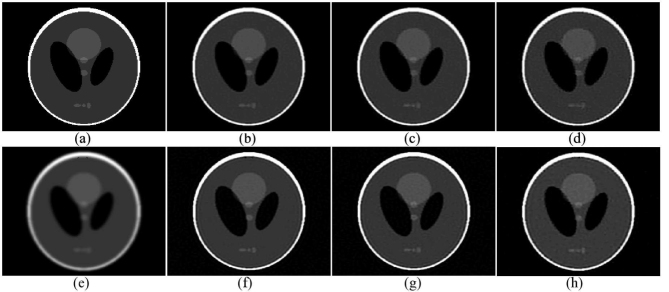

The performance of the proposed compressive deconvolution method are evaluated on several simulated and experimental data sets. First, we test our algorithm on a modified Shepp-Logan phantom containing speckle noise to confirm that the lpsubscript𝑙𝑝l_{p}-norm regularization term is more adapted to US images than the generalized TV used in [26]. The approach in [26] is referred as CD_Amizic hereafter. Second, we give the results of our algorithm for different lpsubscript𝑙𝑝l_{p}-norm optimizations on simulated US images, showing the superiority of our approach over the intuitive sequential method explained in section II. Finally, compressive deconvolution results on two in vivo ultrasound images are presented. Moreover, a comparison between our approach and CD_Amizic on the standard Shepp-Logan phantom is provided in Appendix C.

III-A Results on modified Shepp-Logan phantom

We modified the Shepp-Logan phantom in order to simulate the speckle noise that degrades in practice the US images. For this, we followed the procedure classically used in US imaging [45]. First, scatterers at uniformly random locations have been generated, with amplitudes distributed according to a zero-mean generalized Gaussian distribution (GGD) with the shape parameter set to 1.3 and the scale parameter equal to 1. The scatterer amplitudes were further multiplied by the values of the original Shepp-Logan phantom pixels located at the closest positions to the scatterers. The resulting image, mimicking the tissue reflectivty function (TRF) in US imaging, is shown in Fig.1(a). The blurred image in Fig.1(b) was obtained by 2D convolution between the TRF and a spatially invariant PSF generated with Field II [46], a state-of-the-art simulator in US imaging. It corresponds to a 3.5 MHz linear probe, sampled in the axial direction at 20 MHz. The compressive measurements were obtained by projecting the blurred image onto SRM and by adding a Gaussian noise corresponding to a SNR of 404040 dB.

Reconstruction results for a CS ratio of 0.60.60.6 are shown in Fig.1. They were obtained with: the recent compressive deconvolution technique reported in [26] (referred as CD_Amizic), the proposed method using the generalized TV prior (denoted by ADMM_GTV) and the proposed method using the lpsubscript𝑙𝑝l_{p}-norm for p𝑝p equal to 1.5, 1.3 and 1 (denoted respectively by ADMM_L1.5, ADMM_L1.3 and ADMM_L1). All the hyperparameters were set to their best possible values by cross-validation. For CD_Amizic, {β,α,η,τ}={107,1,104,102}𝛽𝛼𝜂𝜏superscript1071superscript104superscript102\{\beta,\alpha,\eta,\tau\}=\{10^{7},1,10^{4},10^{2}\}. For ADMM_GTV {μ,α,β}={105,2×101,102}𝜇𝛼𝛽superscript1052superscript101superscript102\{\mu,\alpha,\beta\}=\{10^{-5},2\times 10^{-1},10^{2}\} and for the proposed method with lpsubscript𝑙𝑝l_{p}-norms, {μ,α,β,γ}={105,2×101,101,3×102}𝜇𝛼𝛽𝛾superscript1052superscript101superscript1013superscript102\{\mu,\alpha,\beta,\gamma\}=\{10^{-5},2\times 10^{-1},10^{1},3\times 10^{-2}\} . The quantitative results for different CS ratios are regrouped in Table.I. They confirm that the lpsubscript𝑙𝑝l_{p}-norm is better adapted to recover the TRF in US imaging than the generalized TV. The difference between the two priors is further accentuated when the CS ratio decreases.

Keeping in mind that the generalized TV prior is not well suited to model the TRF in US imaging, we did not use CD_Amizic in the following sections dealing with simulated and experimental US images. Moreover, the proposed method was only evaluated in its lpsubscript𝑙𝑝l_{p}-norm minimization form.

Refer to caption

Figure 1: Reconstruction results for SNR = 40dB and a CS ratio of 0.6. (a) Modified Shepp-Logan phantom containing random scatterers (TRF), (b) Degraded image by convolution with a simulated US PSF, (c) Reconstruction result with CD_Amizic, (d) Reconstruction result with the proposed method using a generalized TV prior (ADMM_GTV), (e, f, g) Reconstruction results with the proposed method using an lpsubscript𝑙𝑝l_{p}-norm prior, for p𝑝p equal to 1.5, 1.3 and 1 (ADMM_L1.5, ADMM_L1.3 and ADMM_L1).

TABLE I: Quatitative results for the modified Shepp-Logan phantom with US speckle (SNR = 40dB)

CS ratios CD_Amizic ADMM_GTV ADMM_L1.5 ADMM_L1.3 ADMM_L1

80% PSNR 30.82 31.11 32.23 32.32 32.05

SSIM 83.24 85.03 86.44 88.77 87.70

60% PSNR 29.68 29.83 31.27 31.50 31.32

SSIM 74.58 77.83 82.26 86.03 85.64

40% PSNR 26.76 28.11 29.58 30.04 30.12

SSIM 43.43 61.46 73.88 79.95 81.75

20% PSNR 20.22 21.53 26.81 27.29 28.20

SSIM 8.35 12.77 51.70 62.93 72.34